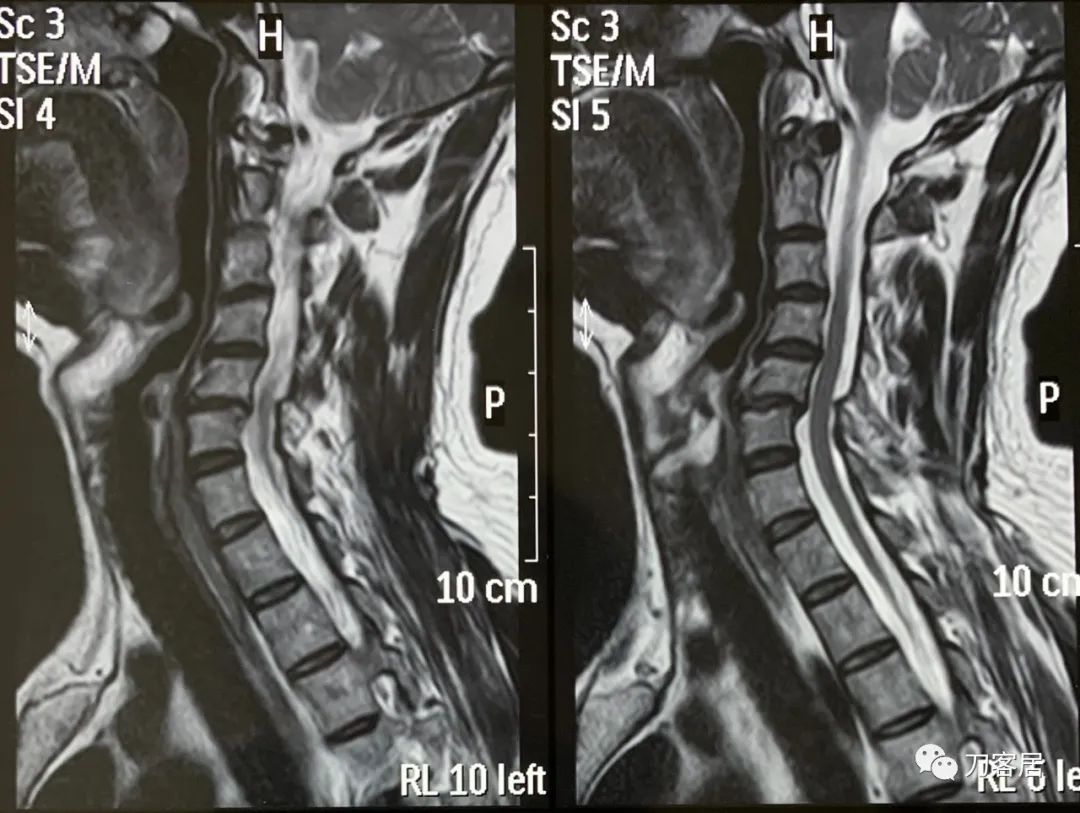

自带颈椎MRI提示颈5-6退变性滑脱,颈5椎体后移,不稳,但患者临床无神经损伤表现,且病程较短,暂不考虑手术治疗,病情变化请随时来就诊。

诊断:颈5-6退变失稳,神经根型颈椎病。

图1. 20160320-QHM-C-A医院颈椎MRI01

图2. 20160320-QHM-C-A医院颈椎MRI02